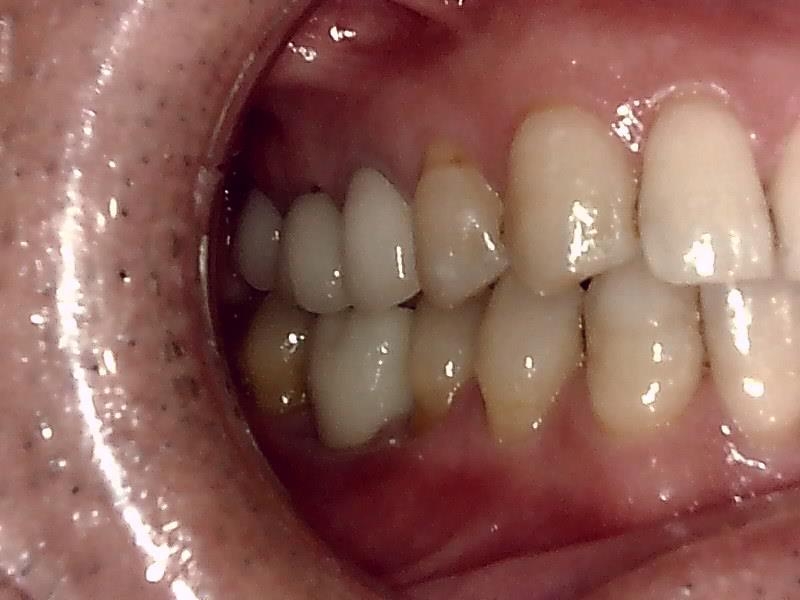

右側面観